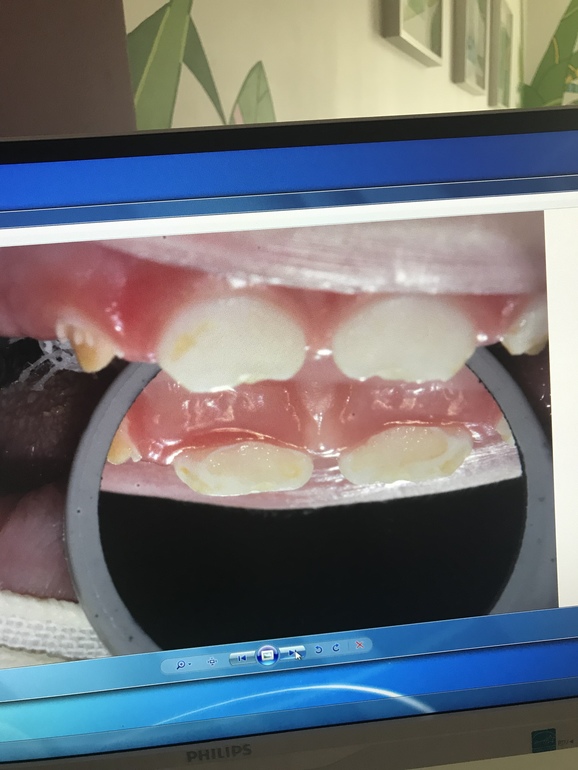

ЗубкиВчера вылечили и реставрировали зубы младшему. 4 зуба из 6... 2 часа под Севоран. Спасибо огромное врачам клиники Ваш Стоматолог они умнички и проделали колоссальную работу! У сына были 2 пульпита и кариес на передних верхних резцах. Обошлось лечение в 33.500₽ . Теперь ребёнок опять может без дискомфорта есть холодное/горячие / кислое / твёрдое ! наркоз перенесли хорошо , в пятницу едем на осмотр после операционный ! Для тех кому интересно приложу фото до и после

Зубки будем по необходимости реставрировать